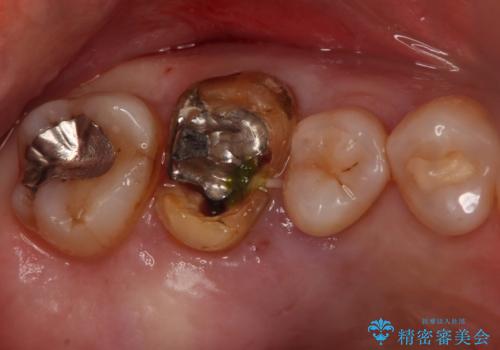

- 症状はないものの、検査の結果右上の奥歯が大きく割れていることが確認されたケースです。

無症状であったため放置していた結果、歯の周囲の骨が溶けてなくなっていました。

歯の深いところまで割れてしまっている場合は健康な状態での歯の保存ができないため抜歯の適応になります。